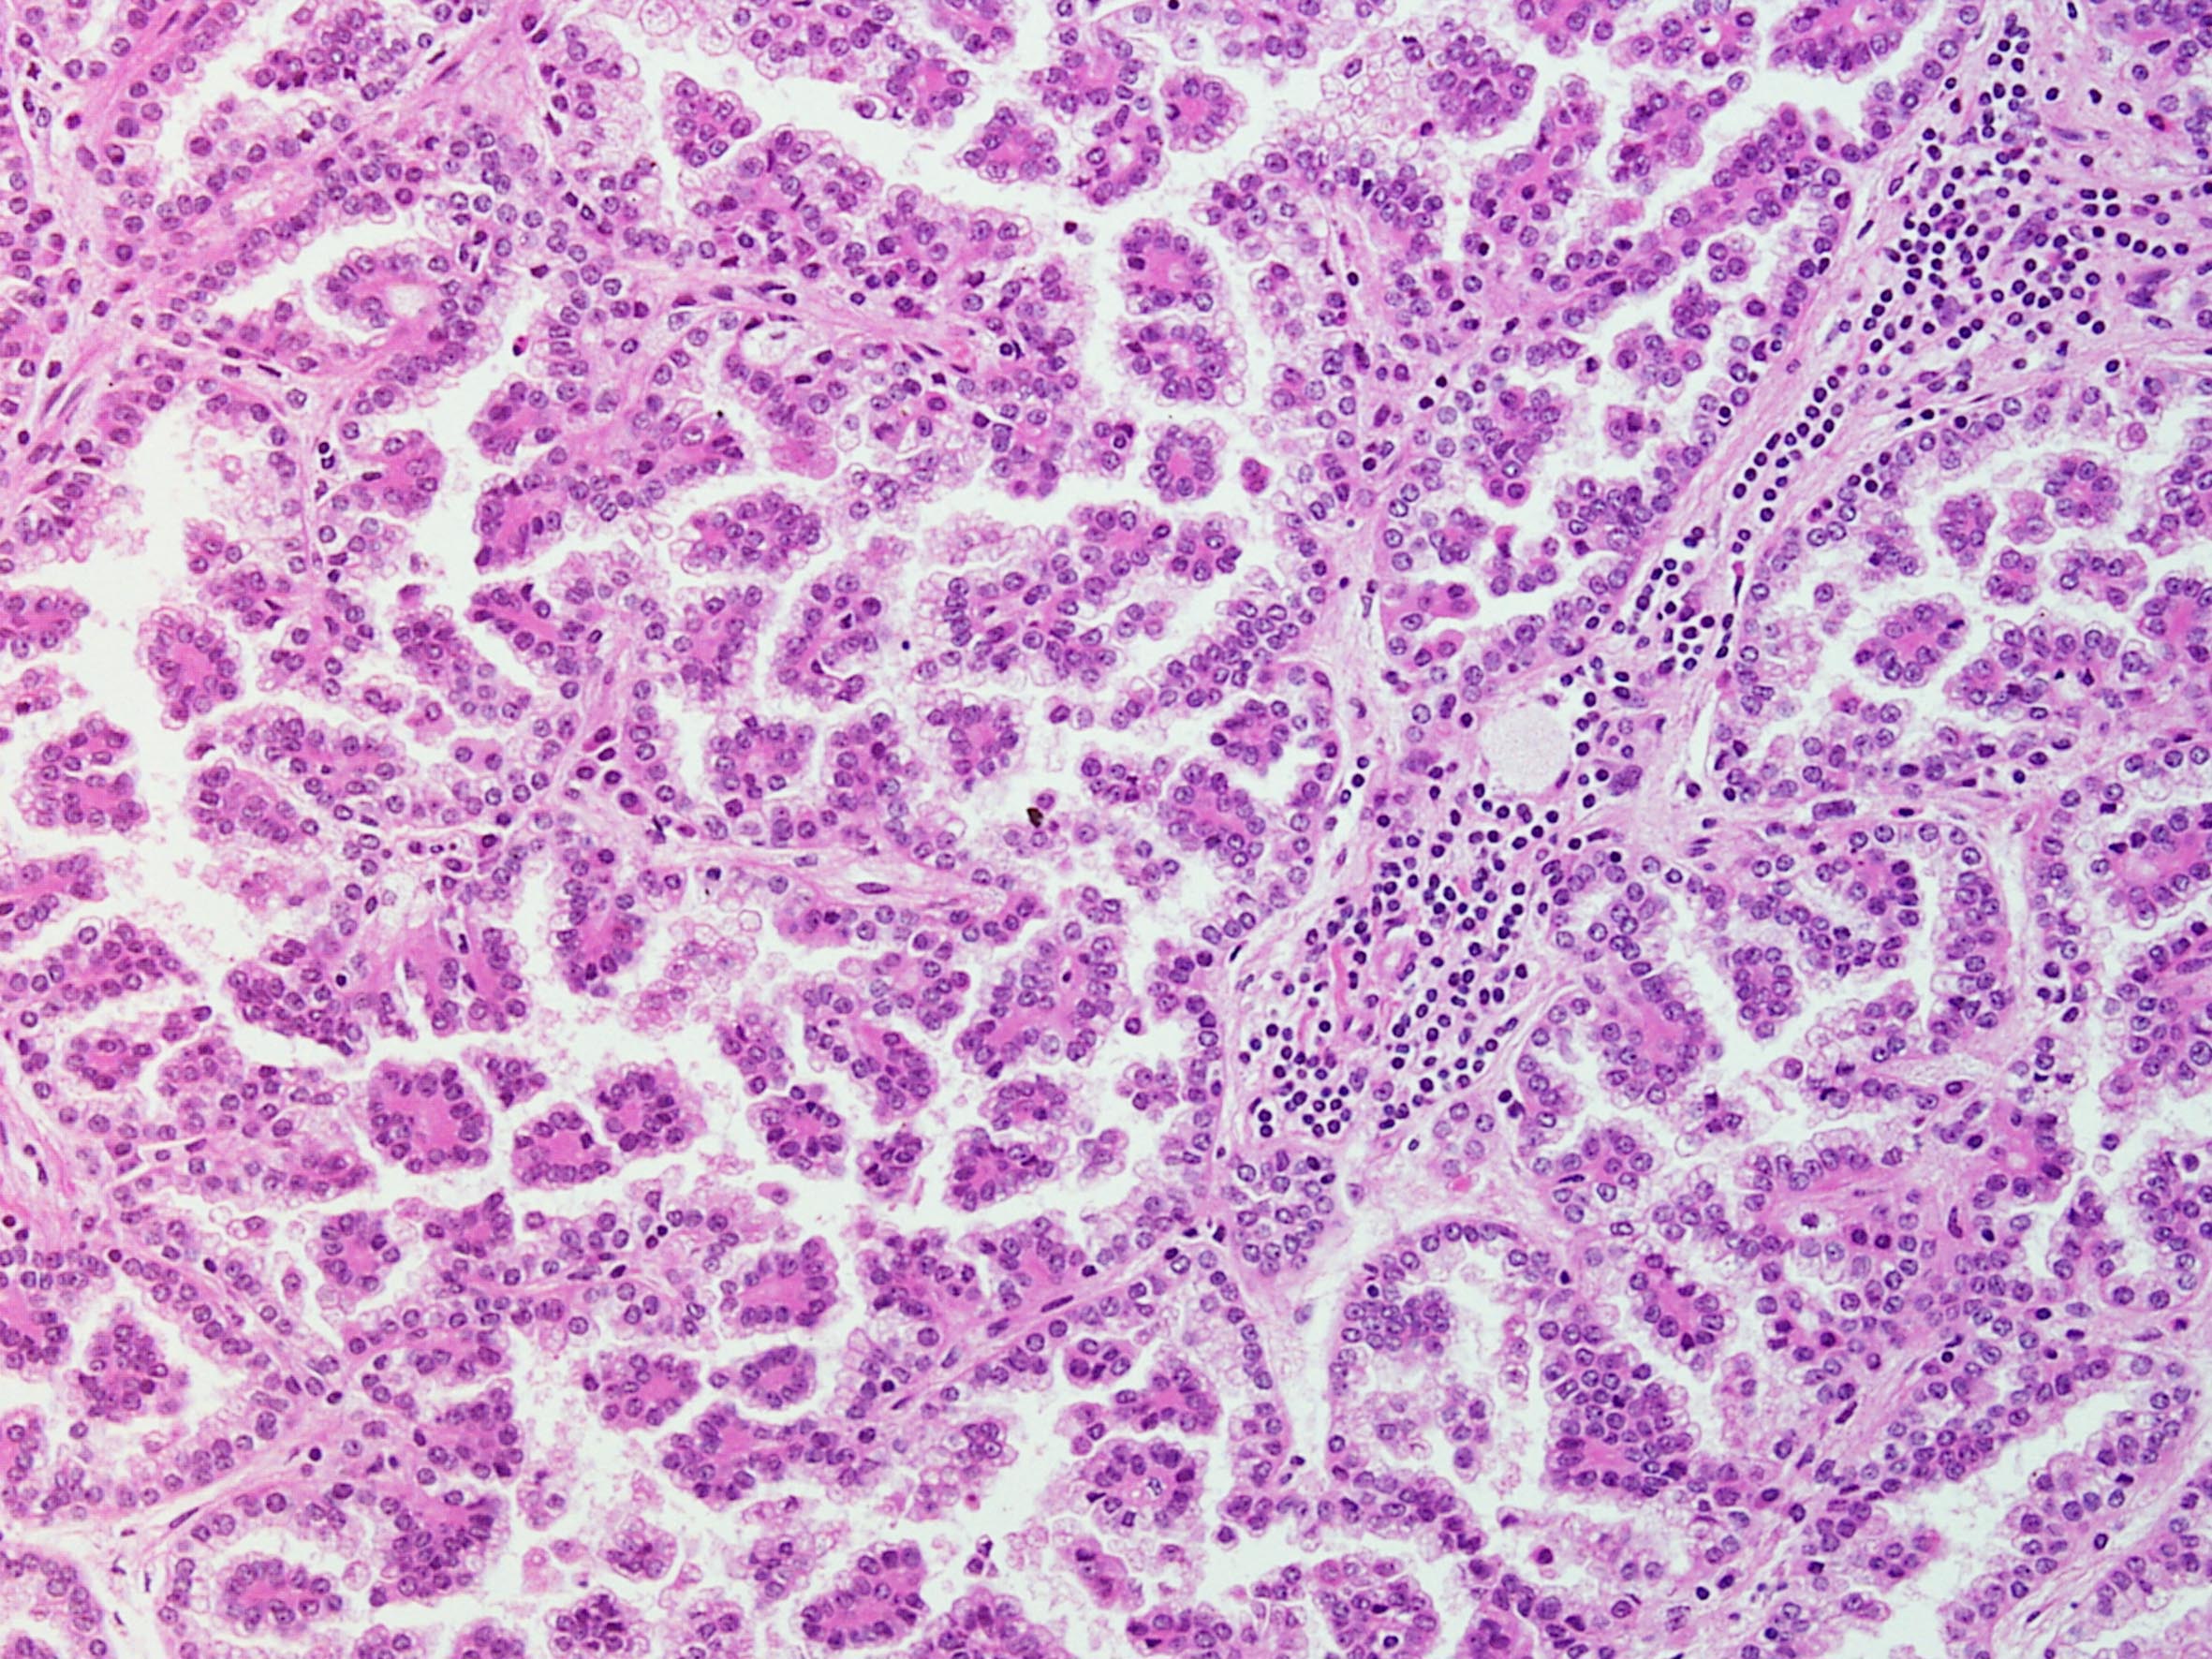

Classification of renal tumors

Case ID: 148